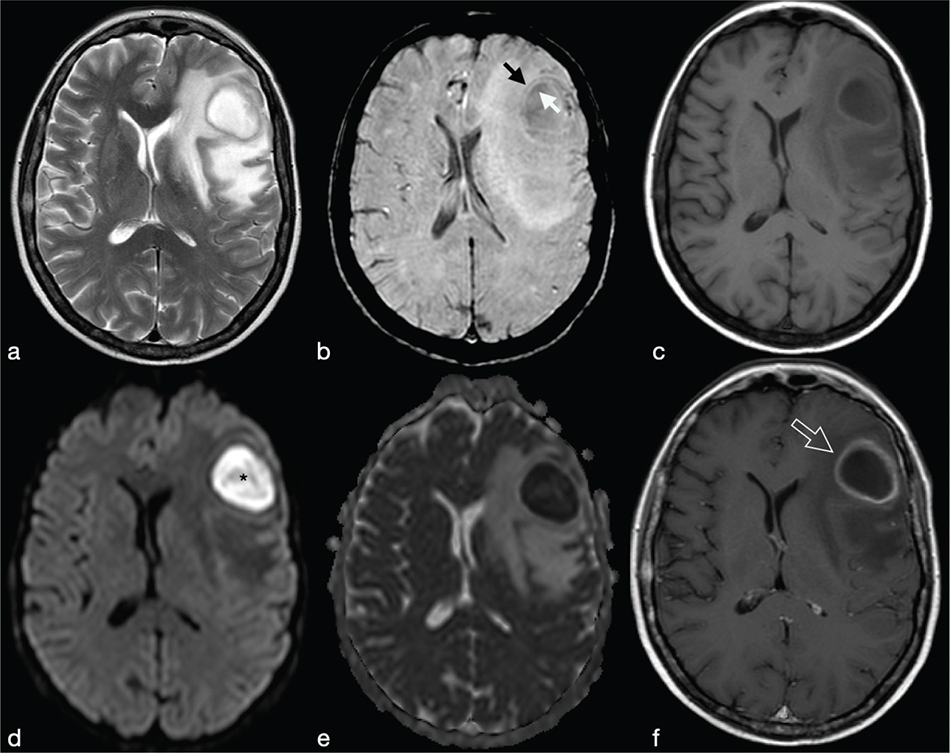

Cerebral toxoplasmosis is typical of immunocompromised patients. MRI shows multiple lesions in different stages of evolution typically located in the subcortical and periventricular white matter, in the basal ganglia and thalami. In particular, two signs are recognised as typical of toxoplasmosis: the “concentric” target sign (concentric alternating hypointense and hyperintense rims in T2w images), and the “eccentric” target sign (peripheral rim of enhancement and focal lateral eccentric enhancing nodule on T1w post-contrast) (Figure 16). On DWI, the centre of the toxoplasma abscess is seen to have ADC values higher than in pyogenic abscesses.22

FIG 16. Multiple Toxoplasma gondii Abscesses in a 45-Year-Old Immunocompromised Woman. T2w (a), T1+Gd (b, f), rCBV map (c), DWI (d) and ADC map (e). Multiple supratentorial brain abscesses in various stages of development with enhancing asymmetric nodules after Gd-injection (“eccentric target sign”) (arrows) can be observed (b, f). Note also the concentric alternating zones of hypo- and hyperintensities on T2w: “concentric target sign” (circle in a). Toxoplasma gondii abscesses typically do not show a core of restricted diffusion on DWI (asterisk in d) while low ADC values may be seen in the capsule (e).